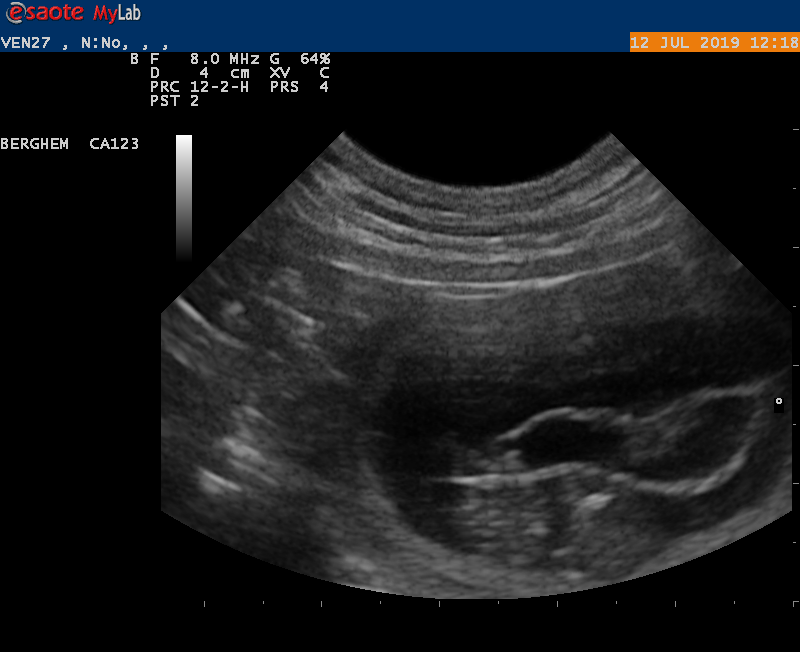

10-6-2021

Vanmiddag zijn we naar de dierenarts geweest met Earke voor een echo. Super goed nieuws: Earke is drachtig. We hebben zelfs al de hartjes zien kloppen van de pups.

Als alles goed blijft gaan krijgen we rond 14 juli een nestje van Earke en Douwe.